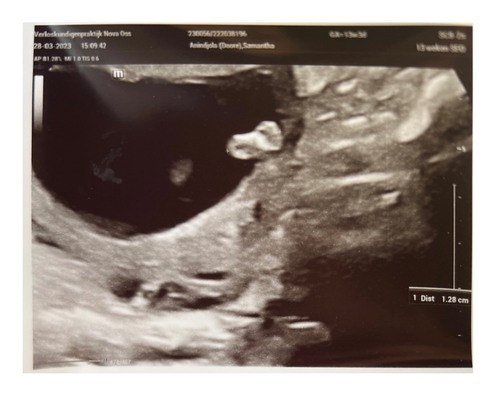

Gisteren de 13 weken echo gehad, ben vandaag 13+4. Alles zag er goed uit en groeide goed, geen opmerkingen zo blij mee. & onze uk zwaaide even naar ons & hebben ook een voetafdruk😜

Het voetje